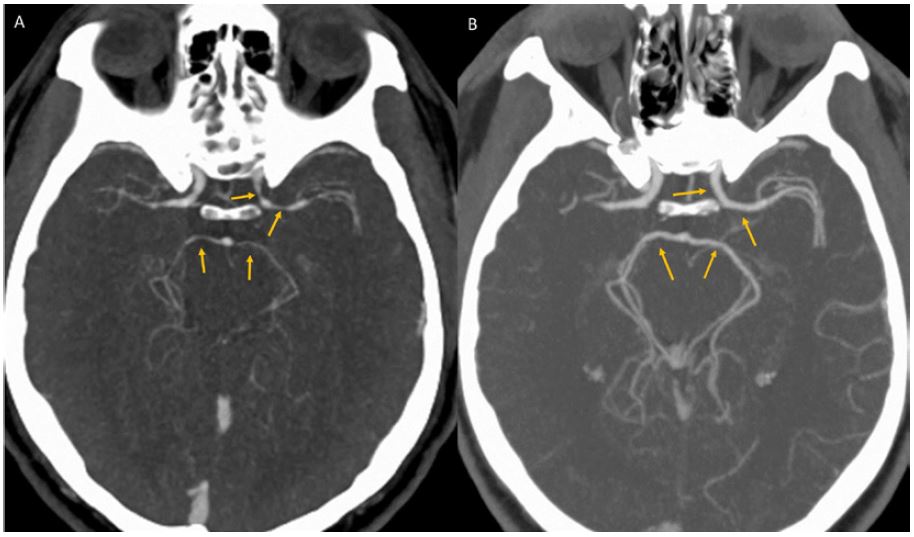

A scan of the man’s brain showing constricted arteries on the left. On the right is the same man’s brain five weeks later, with larger arteries. BMJ Case Reports

A scan of the man’s brain revealed that arteries in his brain were constricted. Doctors ruled out illicit drugs like cocaine and amphetamines as a cause – a common reason for the condition – and ultimately decided that the chili pepper was the culprit.

The man’s symptoms resolved by themselves. Five weeks later, his brain had returned to normal and he reported no further headaches.